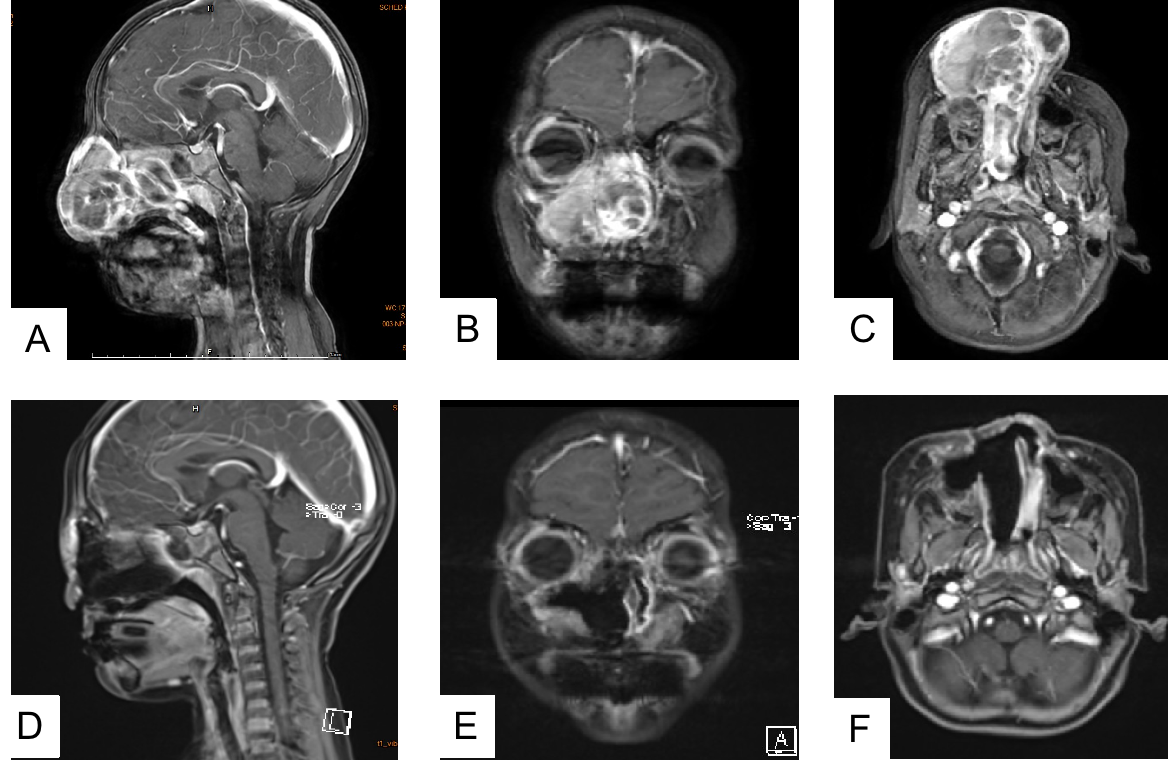

术前(A-C)术后(D-F)核磁共振影像对比

术后病理证实肿瘤被完整切除,影像学复查显示无任何肿瘤残留。雯雯恢复顺利,困扰全家长达一年、令多地专家棘手的罕见顽疾,终于画上了终止符。